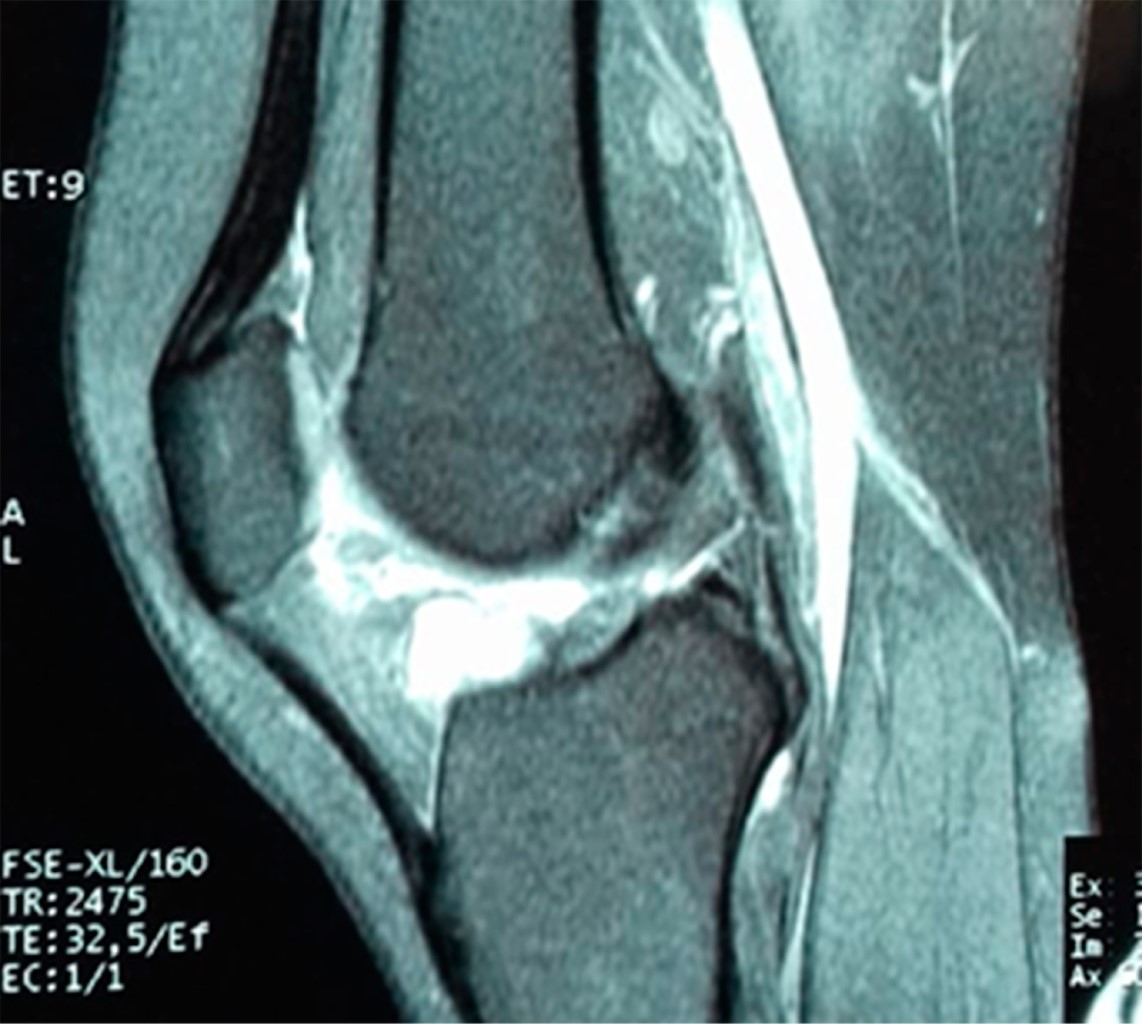

En la exploración física se observa una marcha plantígrada no claudicante independiente tolerando talo equino, rodilla izquierda sin presencia de edema, dolor en línea articular de predominio lateral, el cual se intensifica a la palpación, cajón anterior y posterior negativo, pruebas meniscales McMurray y Appley negativos, Langman negativo, se aplica cuestionario KOOS (Knee Injury and Osteoarthritis Outcome Score), el cual arroja un resultado con limitación funcional impidiendo actividades de la vida diaria, dolor EVA 8/10. Se procede a realizar estudios de imagen: proyecciones radiográficas anteroposterior y lateral de rodilla sin lesiones óseas ni datos de importancia a nivel articular; por antecedente de bloqueo de rodilla se solicita resonancia magnética de miembro izquierdo en la cual se reporta meniscopatía medial grado I a nivel de cuerno posterior, fractura horizontal de cuerno anterior de menisco lateral con formación asociada de gran quiste parameniscal con ejes mayores de 2.7 × 3.7 cm, el resto sin alteraciones (Figuras 1 y 2).

Conviene distinguir entre quistes parameniscales e intrameniscales. La resonancia magnética permite visualizar quistes meniscales en los cortes coronales, sagitales y axiales. Sin embargo, los cortes coronales son los que mejor muestran los quistes, la lesión meniscal y la lesión horizontal comunicante.

La RM se convierte así en el método de estudio de elección cuando se evalúa un posible quiste meniscal, porque informa su localización y tamaño de la lesión meniscal, así como también la existencia de patología asociada extra- e intraarticular.11

Figura 2